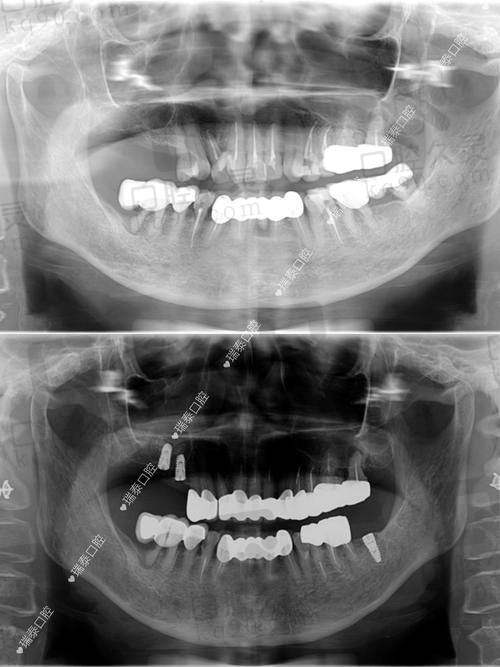

西宁诺贝尔口腔采用的是集成数字化种植体系——三维口腔CT、种植导板系统、口扫设备等一应俱全。尤其是数字化导板技术,能精细定位种植位置,就算是牙槽骨吸收也能放心大胆去种。

提起特色医生团队,我们不得不提种植科的“闫瑞杰”主事,他熟练掌握各大主流系统,如Nobel、Osstem、Straumann等,拥有10年以上复杂种植手术经验,专治“别人做不了”的种牙难题。